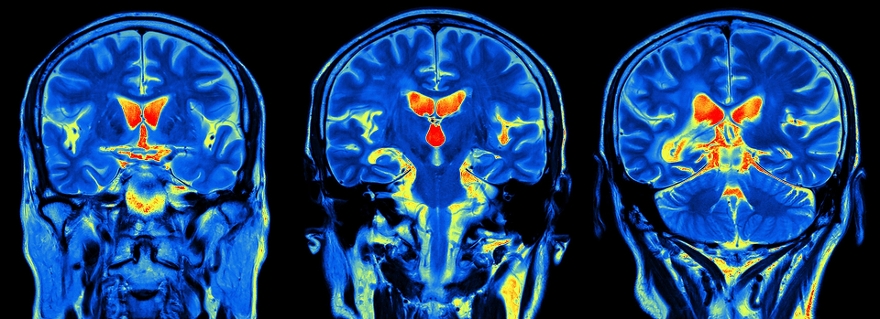

‘Er wordt cognitief neurowetenschappelijk onderzoek gedaan naar de hersenprocessen die ons in staat stellen om van onze geliefden te houden en om op onszelf te reflecteren. Bijvoorbeeld door proefpersonen een functionele MRI-scan te laten ondergaan, terwijl zij naar foto’s van hun geliefden kijken, of aan hen denken. De resultaten uit dergelijk onderzoek gaan dus over hersenprocessen. Het levert inzichten op als ‘bij het kijken naar foto’s van onze geliefden is er activiteit in een dopamine-netwerk in het midden van het brein’. Dat is interessant, maar zulke kennis over hersenactiviteit helpt niet bij het nemen van een besluit over een baan in het buitenland.’

‘Deze mythe is ontstaan naar aanleiding van een experiment waarbij de hersenactiviteit van mensen werd gemeten terwijl ze naar een foto van hun geliefde keken. Die activiteit werd vergeleken met de hersenactiviteit bij het kijken naar een foto van een willekeurige ander. Als proefpersonen naar hun geliefde kijken, is er activiteit in een netwerk in het midden van de hersenen. Datzelfde netwerk is ook actief wanneer iemand cocaïne gebruikt. Zo ontstaat dan de uitspraak dat liefde verslavend is.’